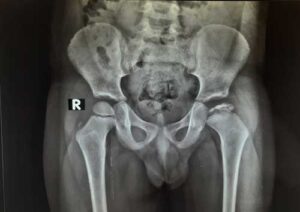

After discussing your child’s symptoms and medical history, your doctor will conduct a thorough physical examination and take x rays of the hip. Usually 1-2 x rays are adequate to make the diagnosis of Perthes disease, but sometimes confirmation diagnosis or treatment planning may need MRI scan of hips.

A child with Perthes can expect to have several x-rays taken periodically over the course of treatment. As the condition progresses, x-rays often look worse before gradual improvement is seen.